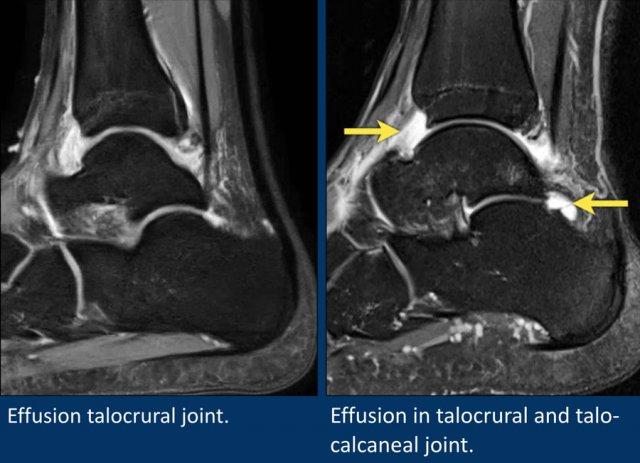

Hai ví dụ về tràn dịch lan tỏa trong khớp chày-sên.

Ngoài ra còn ghi nhận tràn dịch một lượng nhỏ tại khớp sên-gót.